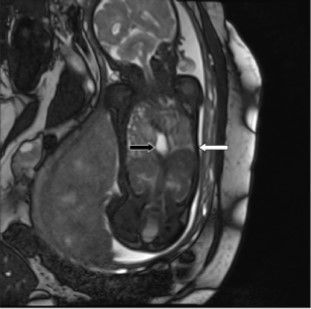

Charts were retrospectively reviewed for observed-to-expected (O/E) values for U/S LHR, MRI FLV measurements, and outcome of the pregnancy and fetus. O/E values normalize measurements to the gestational age of the fetus. MRIs were also retrospectively reviewed by a single pediatric radiologist for location of the stomach. Stomach location was simply defined as all, some, or none of the stomach in the thorax (Figure 2). The primary outcome was survival to discharge. Ultrasound O/E LHR and MRI O/E FLV was compared for all fetuses. An U/S LHR < 1, U/S O/E LHR < 15%, and MRI O/E FLV <25% were considered predictors of poor outcome, and these values were utilized to determine if the various measurements correlated.

Figure 2.MRI demonstrating the entire fetal stomach (black arrow) in the thoracic cavity. The white arrow points to the fetal diaphragm.